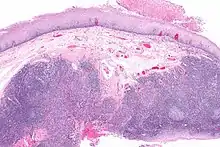

Diagnosis of oral cancer is completed for (1) initial diagnosis, (2) staging, and (3) treatment planning. A complete history, and clinical examination is first completed, then a wedge of tissue is cut from the suspicious lesion for tissue diagnosis. This might be done with scalpel biopsy, punch biopsy, fine or core needle biopsy. In this procedure, the surgeon cuts all, or a piece of the tissue, to have it examined under a microscope by a pathologist.[33] Brush biopsies are not considered accurate for the diagnosis of oral cancer.[34]

With the first biopsy, the pathologist will provide a tissue diagnosis (e.g. squamous cell carcinoma), and classify the cell structure. They may add additional information that can be used in staging, and treatment planning, such as the mitotic rate, the depth of invasion, and the HPV status of the tissue.

From these collective findings, taken in consideration with the health and desires of the person, the cancer team develops a plan for treatment. Since most oral cancers require surgical removal, a second set of histopathologic tests will be completed on any tumor removed to determine the prognosis, need for additional surgery, chemotherapy, radiation, immunotherapy, or other interventions.